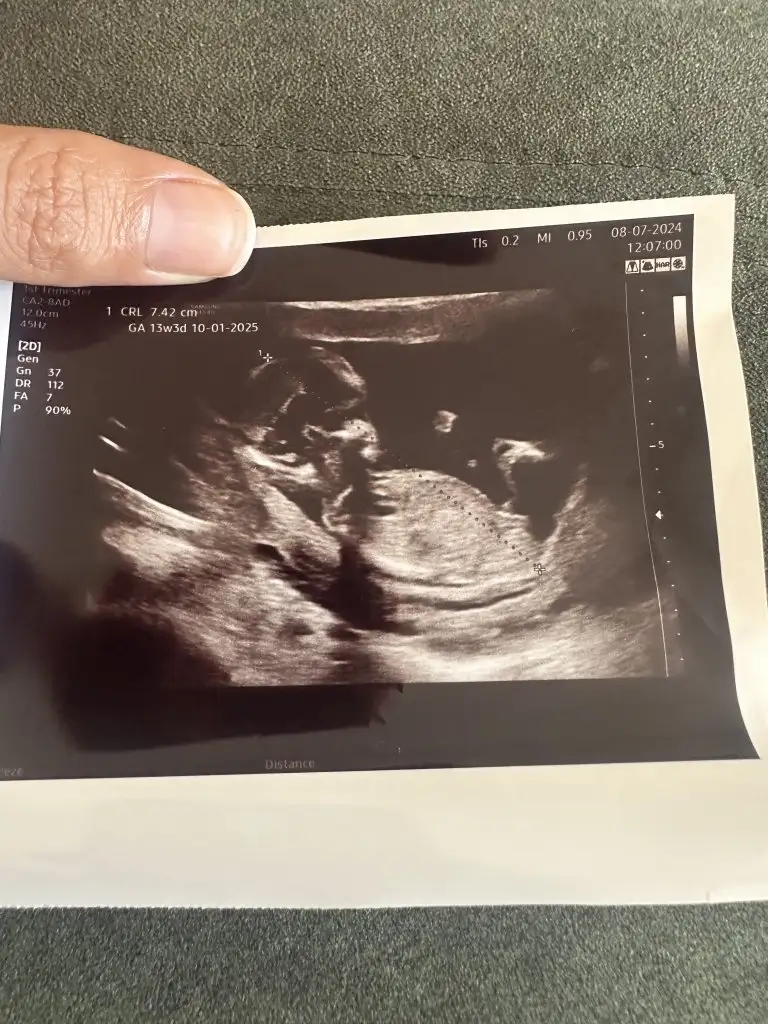

Canim 13 haftalik bakarmisiniz

Eklentiler

• IMG_5072.webp

40 KB · Görüntüleme: 35

• IMG_5071.webp

20,1 KB · Görüntüleme: 33

• IMG_5070.webp

27,2 KB · Görüntüleme: 35